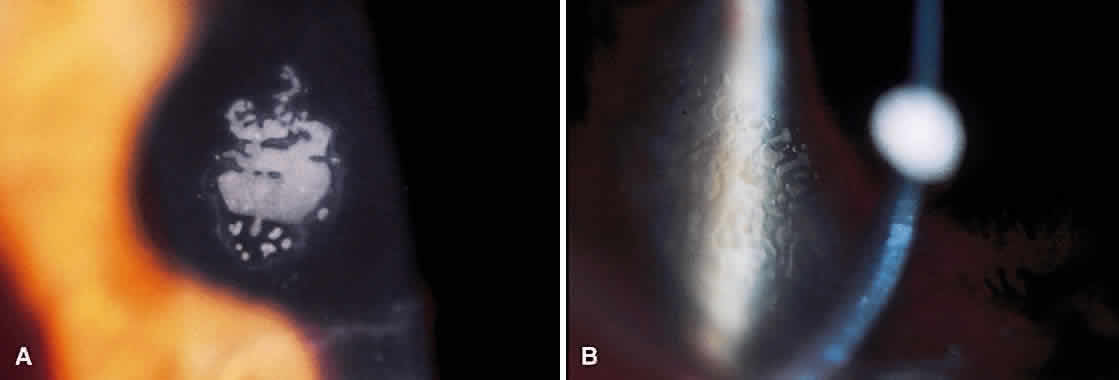

Until the epithelium completely heals, the risk of postoperative infection is greatest. Post-RK bacterial keratitis is primarily the result of the break in epithelial barrier created by the incisions. Adherence of causative organisms to the denuded epithelium over radial incisions can lead to infectious keratitis (Fig. 2). Recently, Panda and colleagues11 highlighted the severity of bacterial keratitis, despite its low incidence. They reported nine cases of post-RK bacterial keratitis at a tertiary-care cornea service during a 9-year period. Four of the nine cases followed primary RK and five followed enhancement procedures. Therapeutic penetrating keratoplasty was performed in one patient. Four of the nine eyes required subsequent penetrating keratoplasty, and one required lamellar keratoplasty. All but one eye retained 20/60 vision or better. These results are discouraging, but the actual incidence of bacterial keratitis lies somewhere between 0% and 0.4%.9,12–14 The PERK study found only 3 cases of bacterial keratitis in 793 eyes (0.38%); all occurred more than 7 months after surgery. All cases occurred in inferior incisions, and only one was spontaneous (one case with contact lens use and another with ocular trauma). None of the three eyes lost BSCVA. Hoffer and associates14 reported only one case of corneal ulcer after RK in 134 procedures performed at Jules Stein.

Post-RK bacterial keratitis usually occurs within 2 weeks of the procedure and is caused by virulent bacteria. The most common causative organisms are listed in Table 1. Infiltrates most commonly arise in the RK incision. Culture and Gram stain should be performed, and frequent fortified topical antibiotics that target the most common organisms should be used until the acute infection is under control. These cases of bacterial keratitis can result in significant vision loss, but if treated appropriately these infections can often be controlled with minimal reduction in vision.11,15 If the site of keratitis coincides with an area of microperforation or macroperforation, aggressive therapy and follow-up are required to avoid bacterial endophthalmitis.16–19

An entity unique to RK is a delayed keratitis, seen up to 40 months after surgery.20,21 The cause is unclear, because each case was associated with positive bacterial cultures. Several cases were associated with contact lens use, inducing microtrauma to the corneal epithelium. Aside from an infectious cause, some theorize that epithelial plugs in RK incisions contain cysts that rupture, leading to sterile inflammation. These cases of sterile keratitis respond to topical corticosteroids. If postoperative keratitis develops, however, therapy should be aimed at infectious causes before the use of topical steroids.